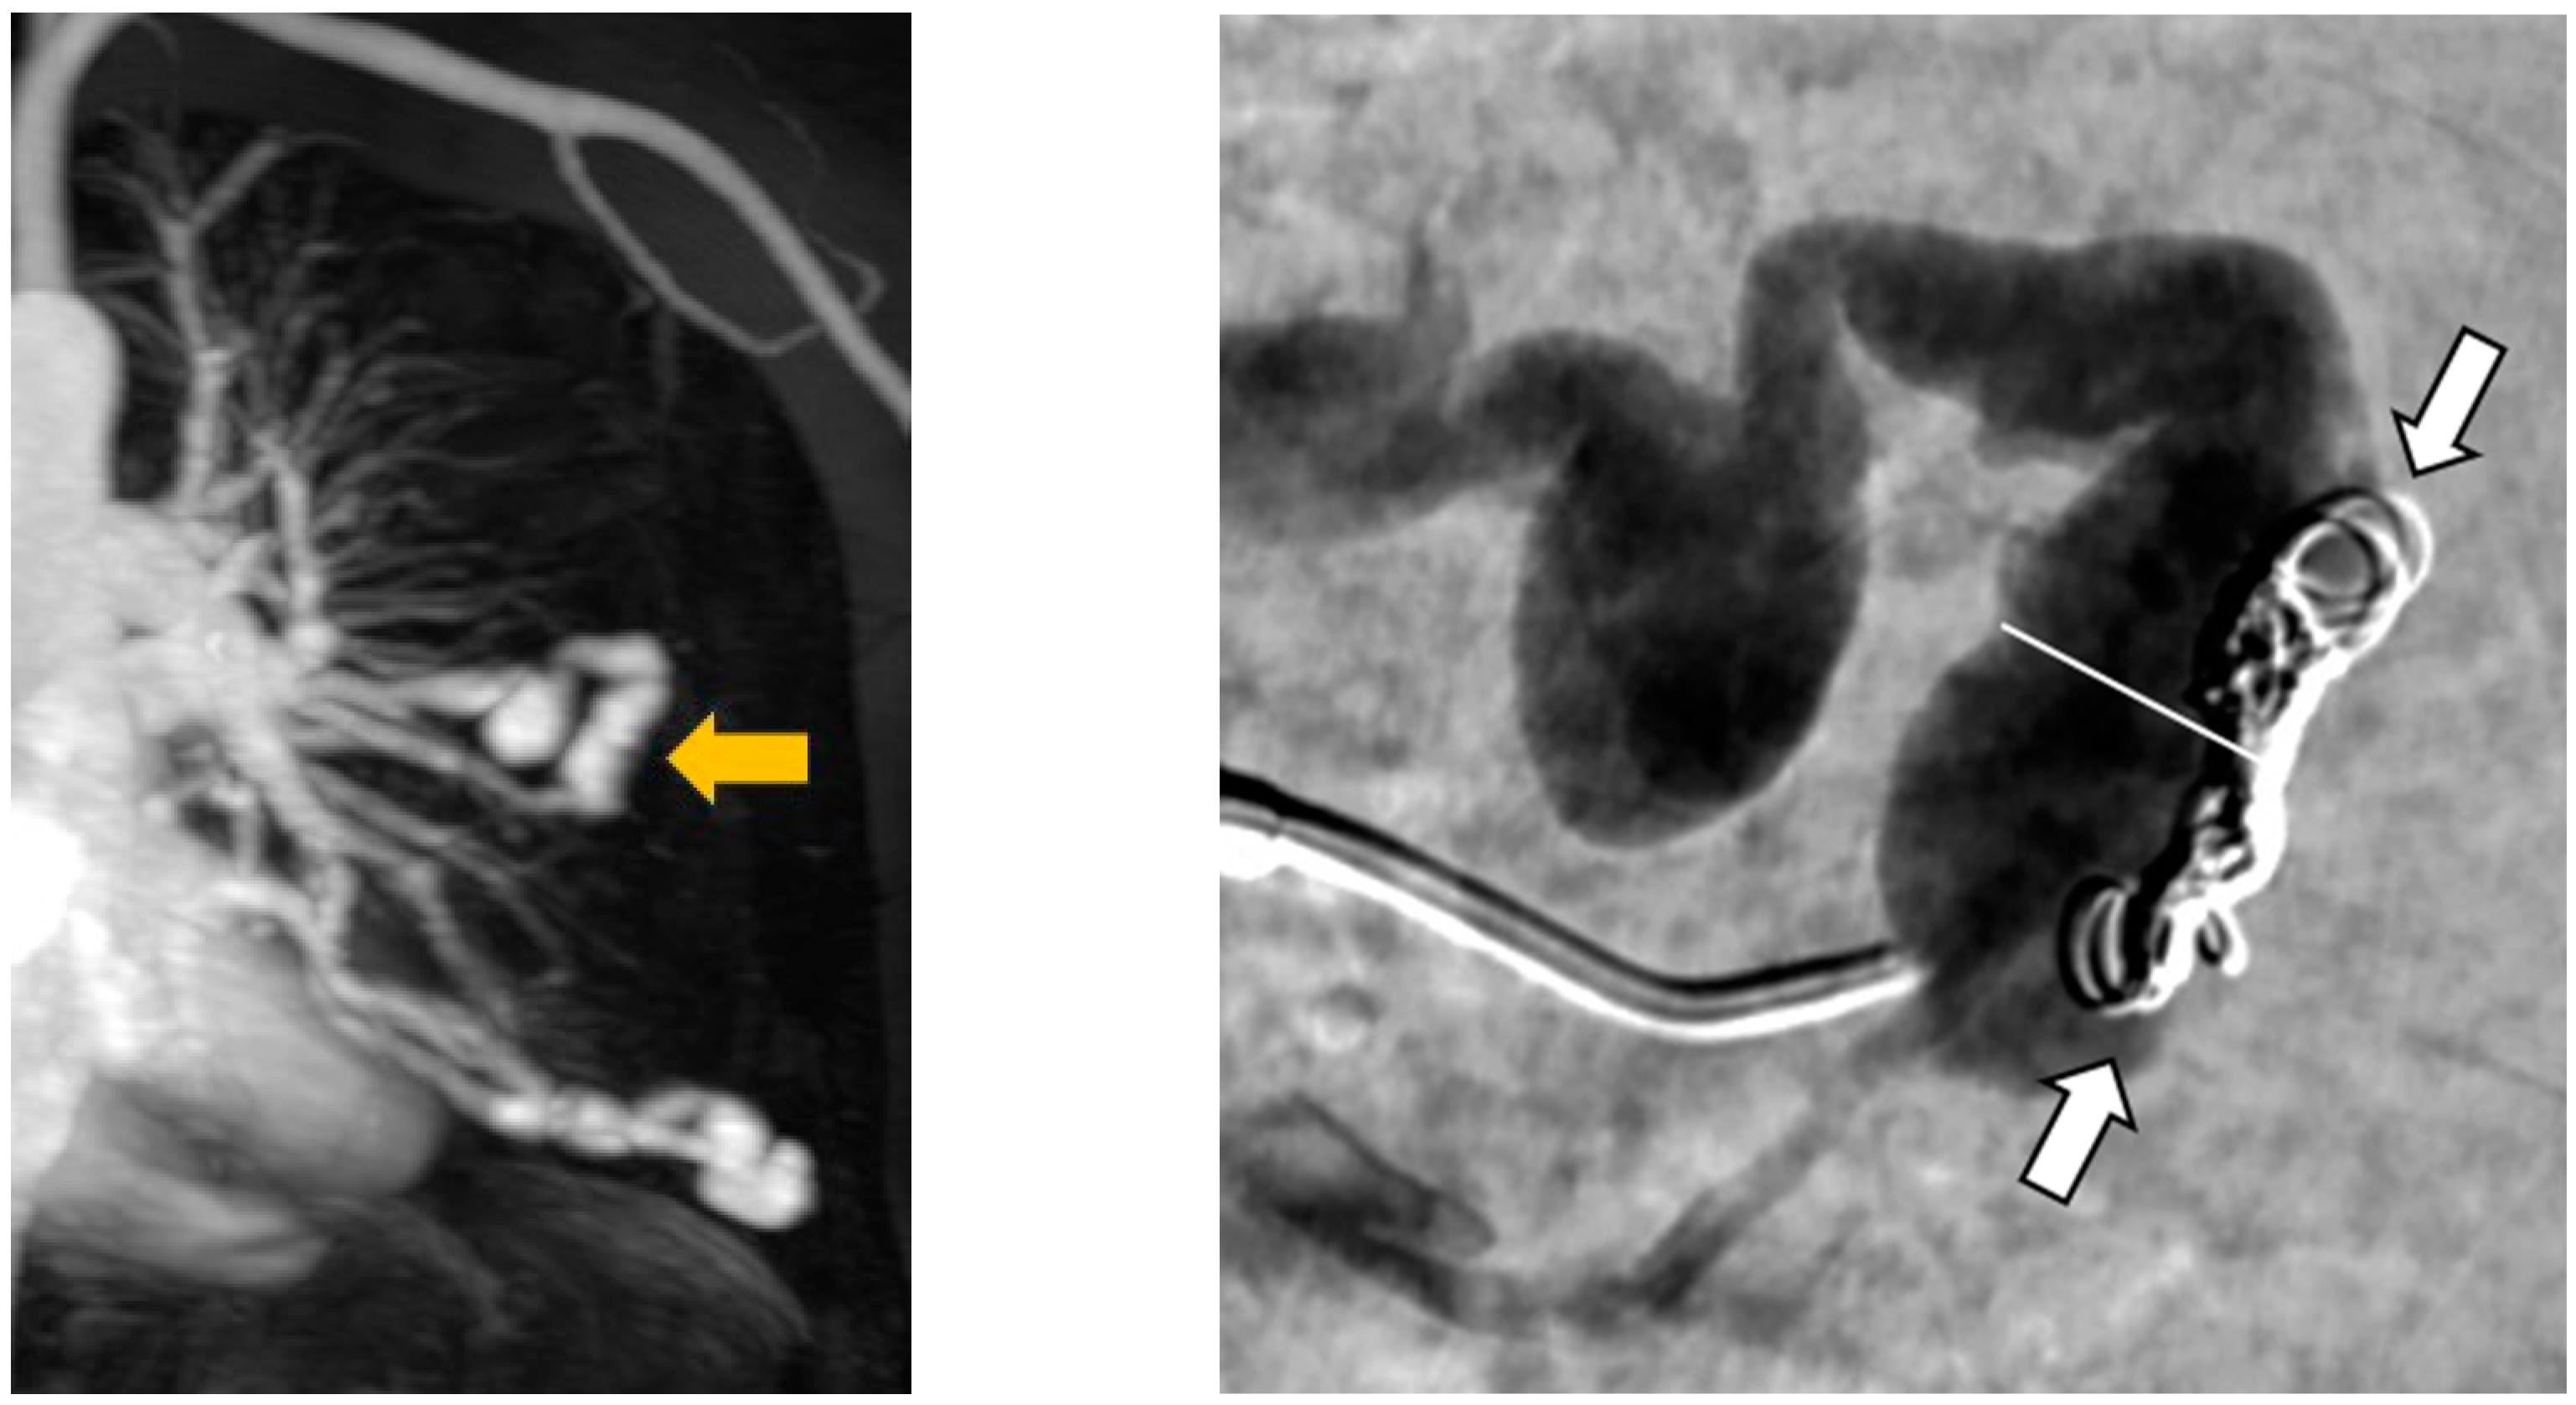

In addition, the recanalization of an Amplatzer™ vascular plug 4 was observed in one malformation. At follow-up visits after three months, one year and four years, this AV shunt was still occluded and recanalization was detected by MRA at a follow-up visit five years and ten months after initial embolization (Figure 10).

Figure 10. DSA of a recanalized AVP 4.